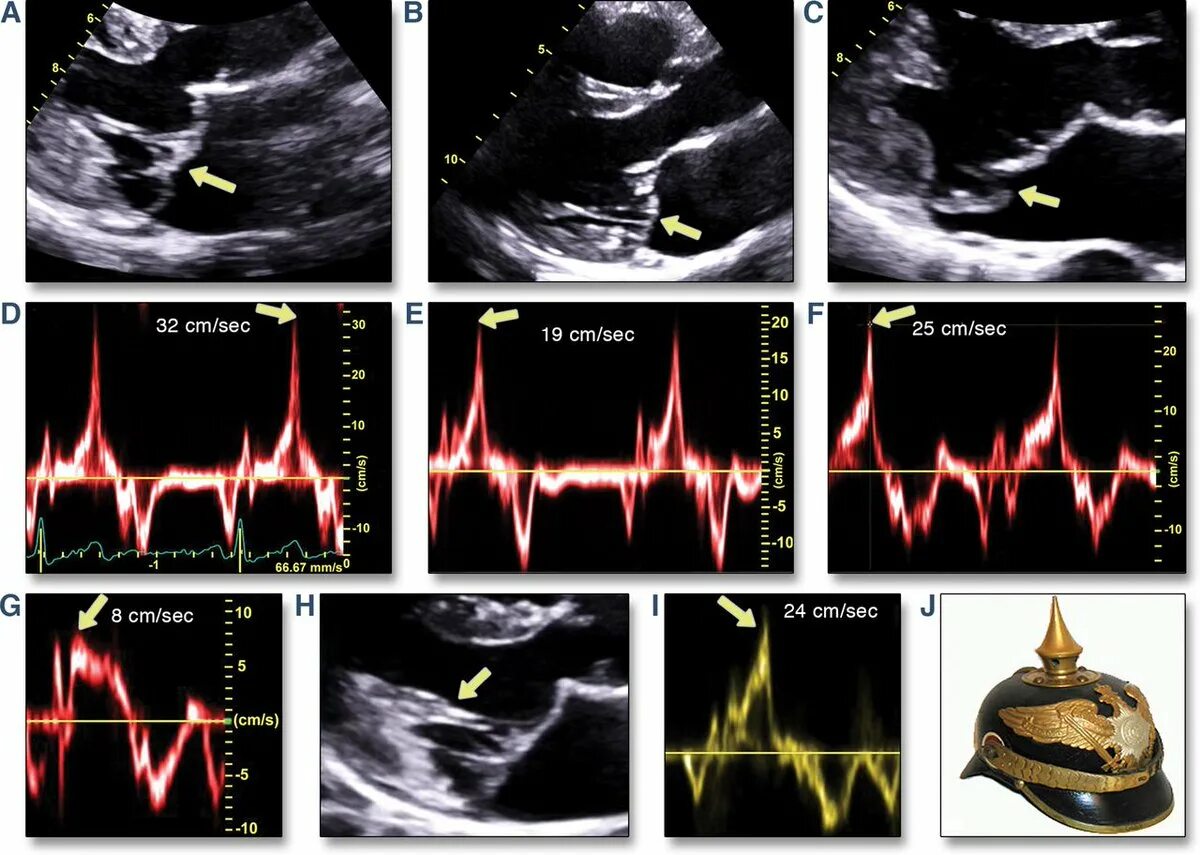

Прогиб створок митрального клапана